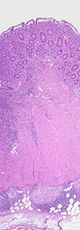

Section of colectomy showing transmural inflammation

غالباً مايعاني المريض لفترة طويلة قبل تشخيص الإصابة بداء كرون . حيث تشترك أعراضه مع أعراض العديد من الأمراض الأخرى ولكن تكرر هذه الأعراض وشدتها توحي بشكل قوي بالتشخيص , إلا أن التشخيص الأكيد لايتم بسهولة . يساعد على وضع التشخيص مجموعة من تحاليل الدم والتصوير بالأمواج فوق الصوتية والتصوير بالطبقي المحوري المحوسب وتصوير الأمعاء الدقيقة الظليل والتصوير باستخدام الكبسولة المعوية والتنظير الهضمي ( العلوي والسفلي ) والذي يعتبر الأهم من ناحية التشخيص لأنه يتيح لنا الرؤية العيانية والحصول على عينة للفحص النسيجي.